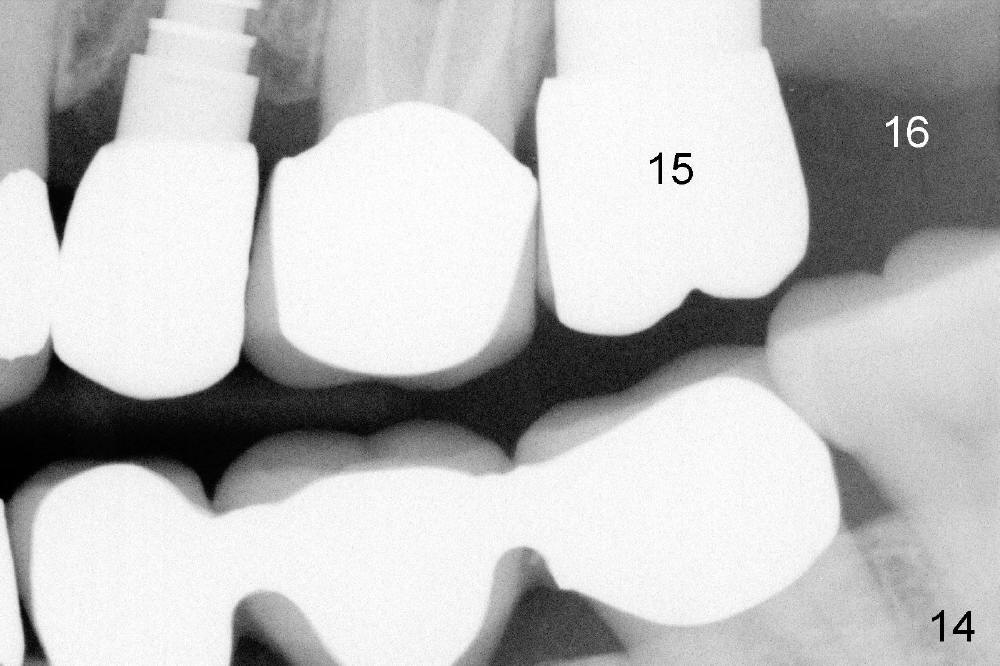

A 66-year-old lady requests restoring a broken tooth (Fig.1). Osteotomy is initiated in a thin septum (Fig.2 (occlusal mirror view) S) by sectioning, drilling and tapping (Fig.3 T). When 7x17 mm tap is removed, the osteotomy is found to form basically in the middle of socket (Fig.4 O). The apical portion of three sockets (Fig.5: MB, P and DB (not labeled) is packed with mixture of autogenous bone and allograft. When a 7x14 mm implant is placed, there are buccal and lingual gaps (Fig.6 *). The latter are bone grafted again (Fig.8 *) and require a coverage. After placement of a 4x3 mm abutment (Fig.7,8 A), an immediate provisional is fabricated (Fig.9 tissue surface view) to cover the remaining sockets (Fig.10 (occlusal mirror view), 11 (buccal view)). The provisional is infra-occlusal, i.e., load-free (Fig.11). The buccal and lingual aspects of the socket are covered by fresh epithelium 8 days postop (Fig.12 <). The implant appears to have osteointegrated 4 months postop (Fig.13). The tooth #16 appears to have shifted mesially. It is difficult to prepare for #15 crown. Luckily the patient agrees to have it extracted because of persistent sensitivity after MO composite. The definitive crown at the site of #15 is cemented 6 months postop (Fig.14).